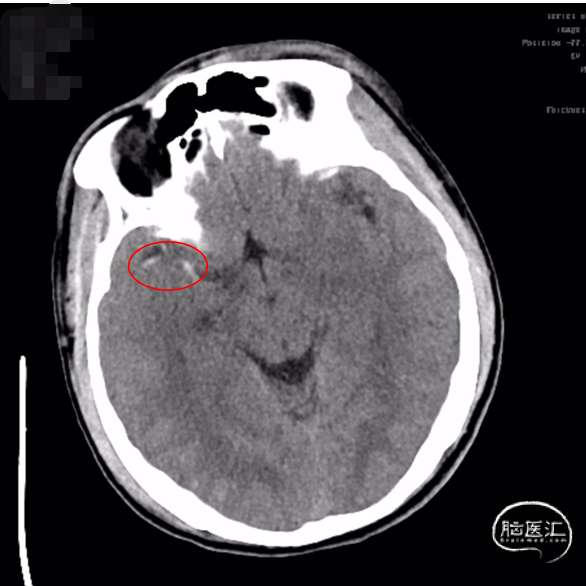

术前影像

ASPECTS评分:8分

右侧大脑中动脉高密度征